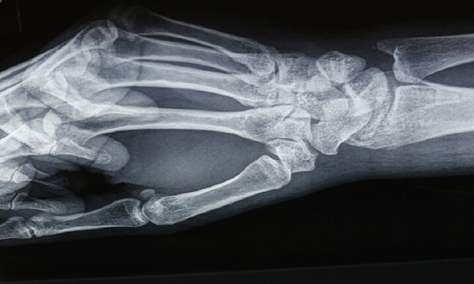

وكشفت الصور الشعاعية ليدَي المريضة عن مدى الضرر الذي أصابها، حيث بدت أصابع اليدين والرسغ والساعد السفلي متآكلة، كما لو أن كميات كبيرة من الأنسجة اختفت.